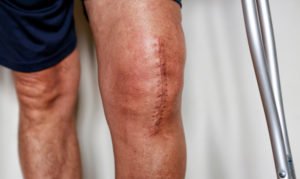

- have undergone – or will undergo – a revision surgery to replace or repair the defective implant.

For as long as you are feeling well and your Exactech hip, ankle or knee replacement device shows no signs of failure, then a revision surgery is not recommended.4

Our legal team is fighting for compensatory damages to cover all your medical expenses, including:

- replacement surgeries